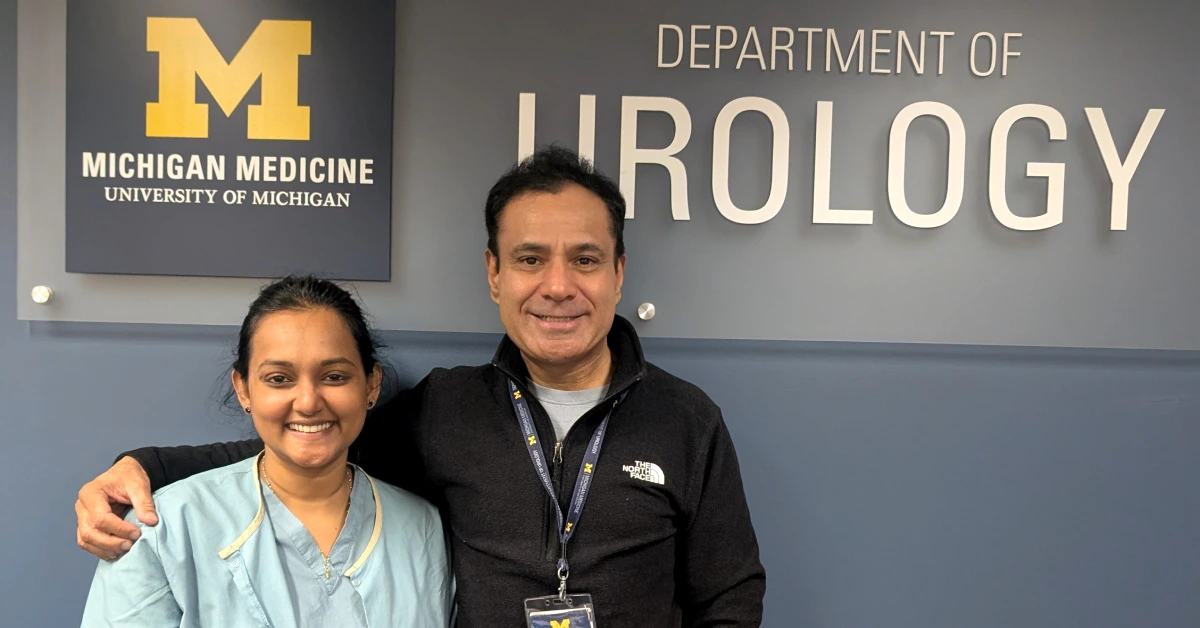

Clinical Observership in the Department of Neuro-Urology and Pelvic Reconstruction - University of Michigan